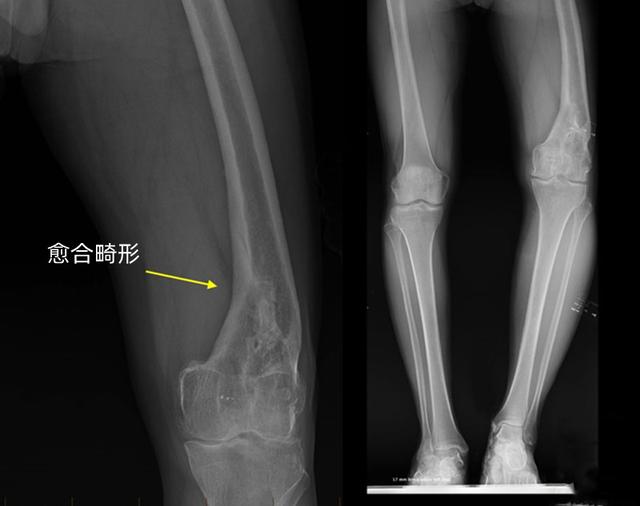

骨折后通常都要进行复位。如果复位或固定不良等其他原因,骨折的断端没有对齐,骨头愈合后不直了,形成了一个角度或者发生了重叠或者旋转,造成一条腿长一条腿短。原因和骨折复位不佳,固定不牢固,过早地拆除固定,还有就是复位的太晚了,骨折已经开始了错误的愈合。

畸形愈合不一定要到康复后才发现,虽然症状各不相同,但在骨折复位后如果出现以下症状,怀疑存在愈合畸形:

骨骼看起来畸形(扭曲,弯曲,旋转或肢体变短)。

不注意这些迹象的话,康复后可能出现腿长不一致,走路跛行,或者脚内旋或外旋,还可能引起臀部,膝盖和脚踝的问题,这是由于畸形愈合打破了下肢的正常力线,其他关节被迫承受过大的压力。

即使骨折处理及时,复位和康复都没问题,也不能完全避免畸形愈合。粉碎性骨折发生时,一块骨头碎裂成好几块,再把它们拼在一起,想按照原来的排列方式完美的组合在一起,存在一定难度。任何类型的骨折越严重,就越容易产生畸形愈合,因为骨头缺乏足够的氧气或营养来促进愈合。

如果出现了畸形愈合,也不一定对以后造成严重影响,每个人的腿长差异本来就不同,只要相差不超过2厘米,基本上不会太影响下肢功能,也不会带来其他关节的疼痛和不适,还有些十几岁的孩子,畸形不严重的情况下也有可能随着生长自行矫正。总之要根据具体情况决定是否需要再次进行手术矫正,畸形矫正手术通常针对以下症状: